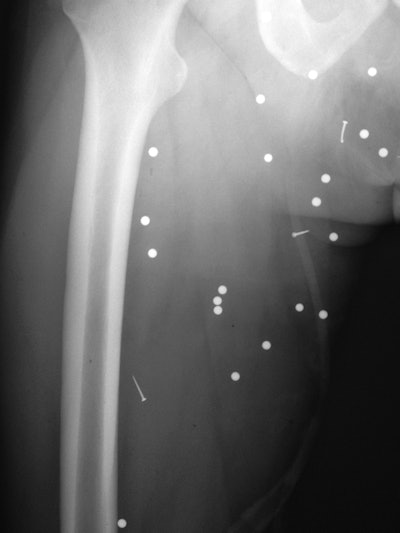

Most of the physical damage came from the secondary blast wave after the initial explosion, Singh and colleagues found. These injuries are more common because the secondary blast wave includes flying debris, such as shrapnel fragments, traveling at high speed.

X-ray and CT showed a total of 189 shrapnel fragments in 32 (74%) of the 43 patients. Most of the objects (153, or 81%) were found in the soft tissues of the legs, thighs, and pelvis, while the remaining 19% were located above the pelvis or in the foot. The number of objects per patient ranged from one to 41 fragments.

Clinicians also found a large variety of debris embedded in patents. There were 125 ball bearings, 44 metal fragments, 10 nails, one screw, and nine pieces of gravel or other foreign objects. In addition, 11 patients had fractures in areas including the foot, leg, thigh, hand, orbit, nose, and lumbar spine. Injuries to five of the patients were so severe that they required lower-limb amputations.

"Because the explosive devices were left on the ground, lower-extremity injuries were the most common, with five patients in our study group requiring lower-limb amputations as a result of their injuries," the authors wrote.